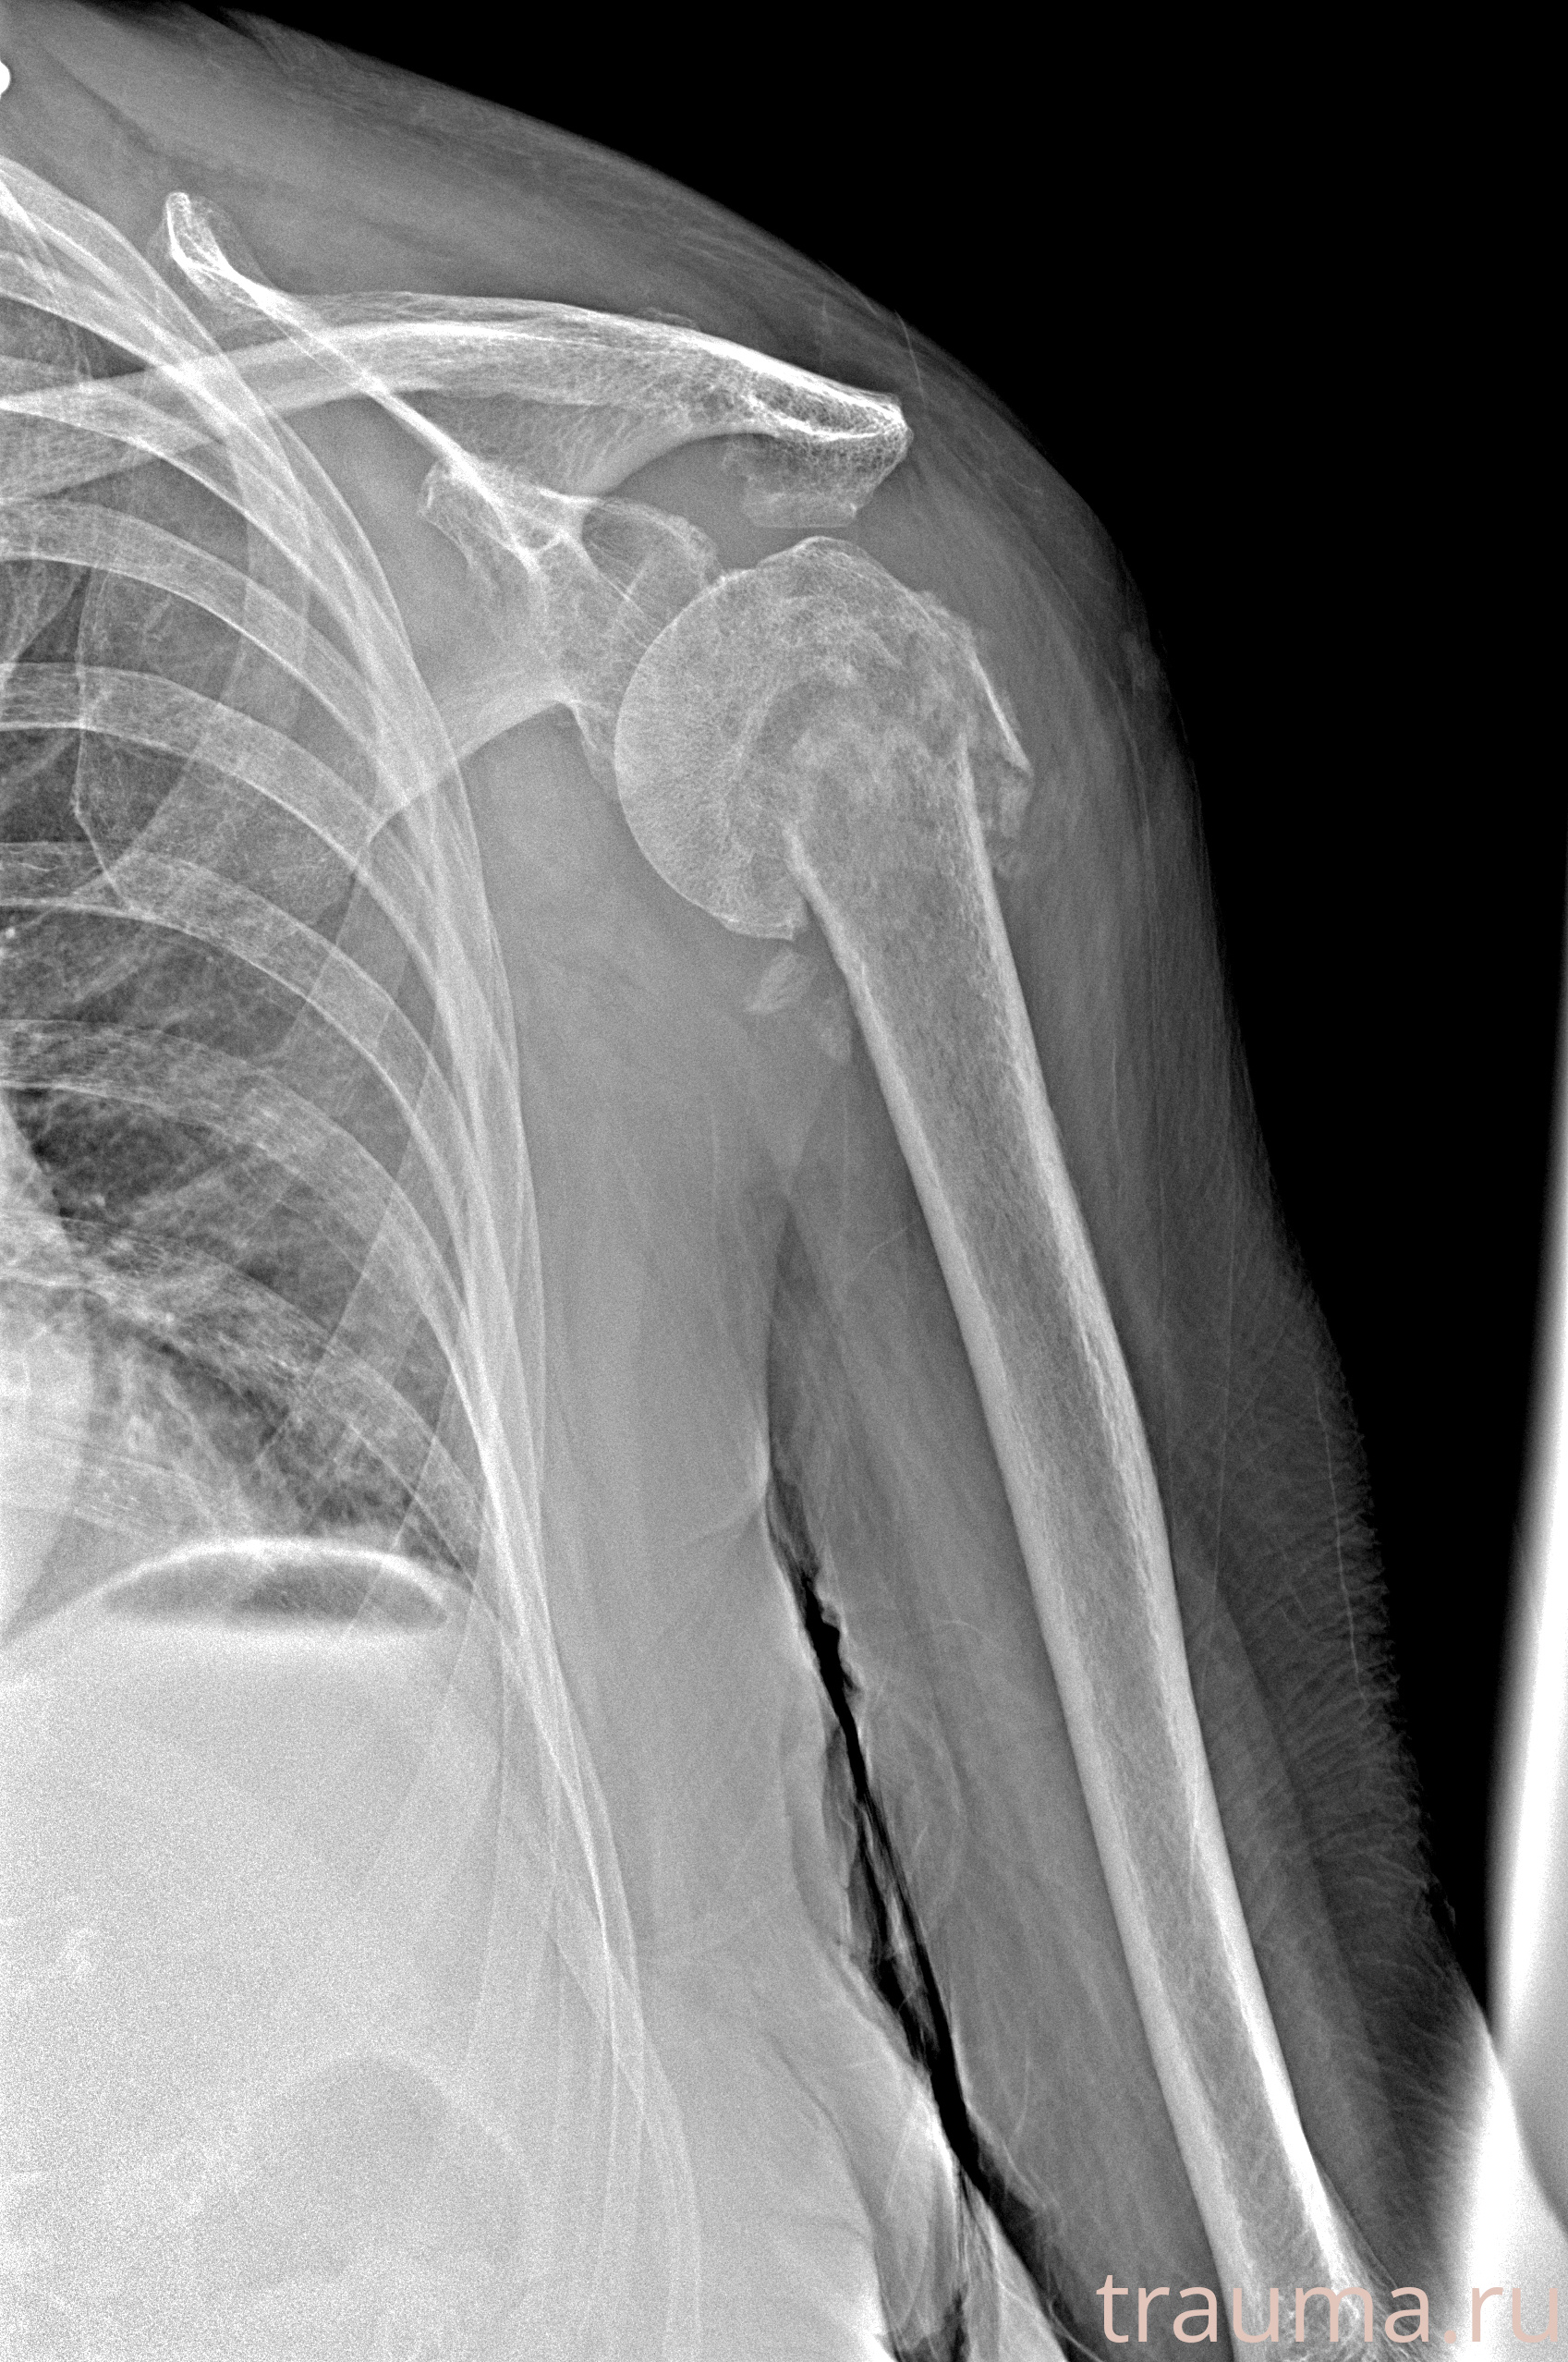

Рентген на дому: по вашему адресу приезжает врач-рентгенолог, травматолог-ортопед с мобильным рентгеновским аппаратом, проводит диагностику травмы или заболевания, делает необходимые рентгенограммы, дает рекомендации по дальнейшему лечению. Получить качественные снимки в домашних условиях возможно благодаря уникальной методике, разработанной МосРентген Центром для института  Склифосовского